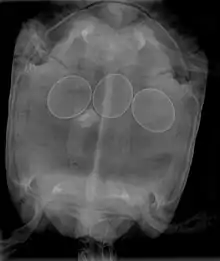

X-ray of a turtle with egg binding.

In reptiles, it is inadvisable to attempt to break a reptile egg to remove it from an egg-bound female. This procedure may be done by a veterinarian, who will insert a needle into the egg, and withdraw the contents with a syringe, allowing the egg to collapse and be removed. Non-surgical interventions include administering oxytocin to improve contractions and allow the egg(s) to pass normally. In many cases, egg-bound reptiles must undergo surgery to have stuck eggs removed.